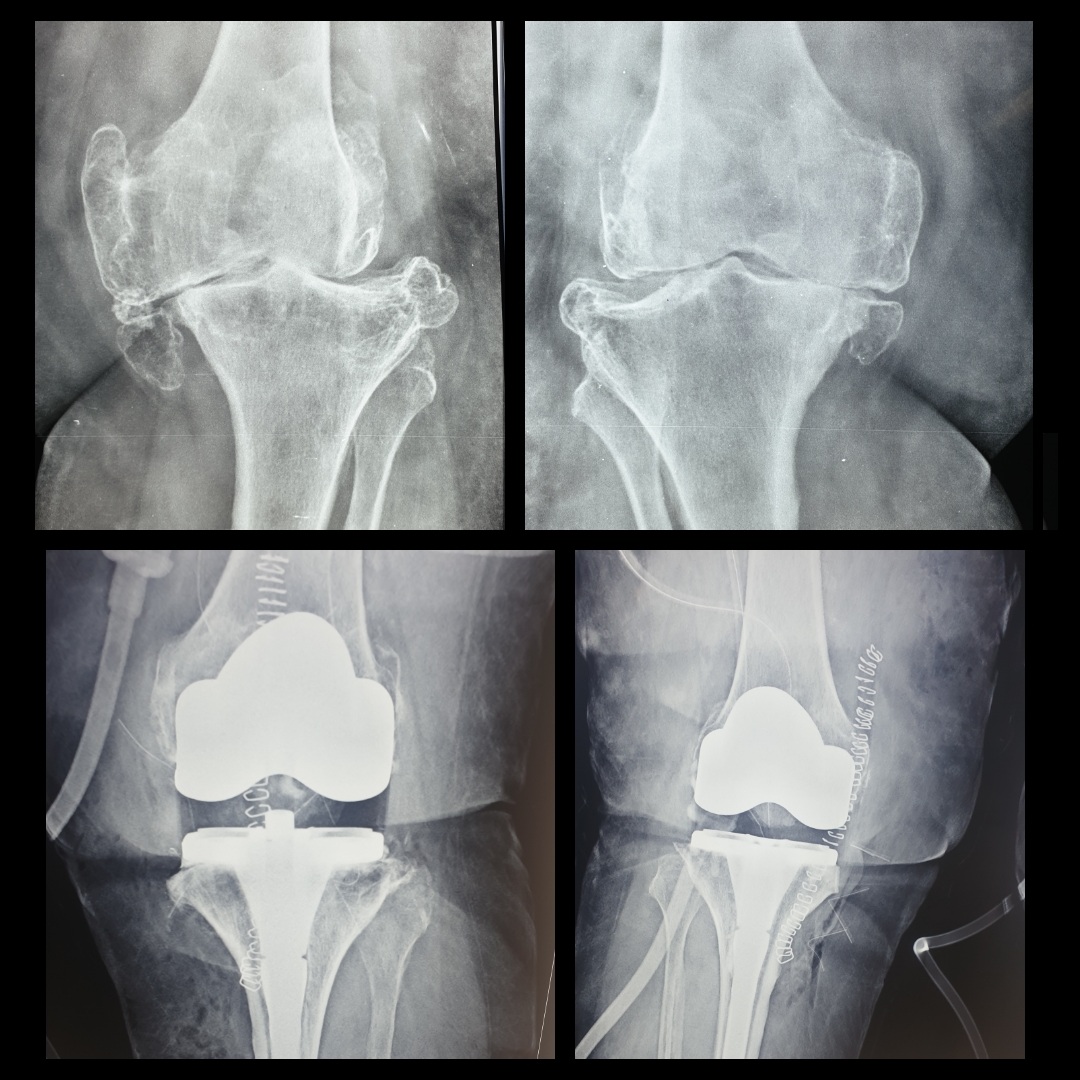

Metal allergies could lead to knee replacement complications

Metal allergies could lead to knee replacement complications When Can I Use Heat On My Knee Replacement If you’ve tried other options, including lifestyle strategies,. The main reason to have it done is pain. Join us as we take a closer look at some of the activities that are best. If you've had total knee replacement (tkr) surgery, you might be wondering if you can. If you’ve just had knee replacement surgery, you can reduce pain and. When Can I Use Heat On My Knee Replacement.